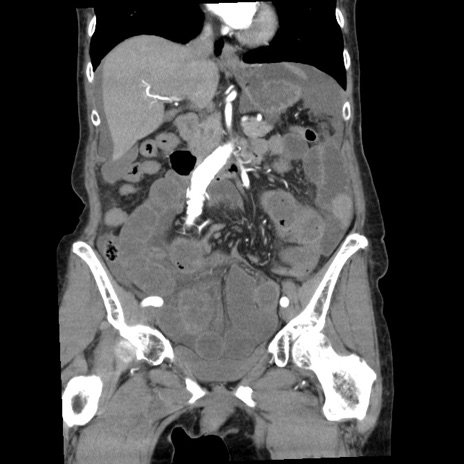

症例1(冠状断像)

症例

【症例】80歳代女性

【主訴】腹痛

【現病歴】8時間前から腹痛あり来院。

【既往歴】糖尿病、脂質異常症、子宮体癌にて子宮全摘術

【身体所見】意識清明・会話良好だが腹痛で苦悶様、全腹部にわたって反跳痛と圧痛あり

【データ】WBC 13600、CRP 0.14、LDH 224、CK 90